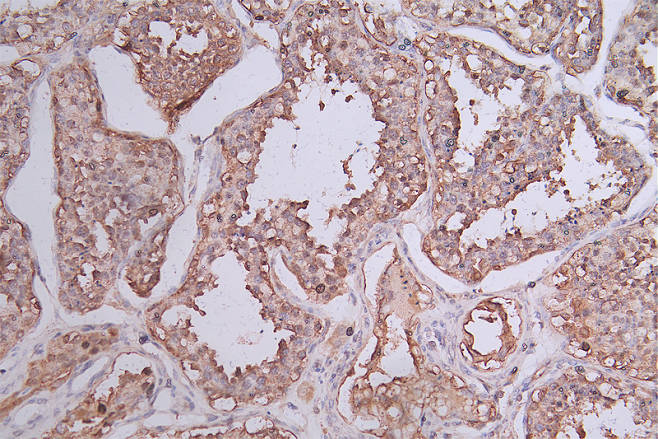

CSB-RA644510A0HU

IHC image of CSB-RA644510A0HU diluted at 1:50 and staining in paraffin-embedded human testis tissue performed on a Leica BondTM system. After dewaxing and hydration, antigen retrieval was mediated by high pressure in a citrate buffer (pH 6.0). Section was blocked with 10% normal goat serum 30min at RT. Then primary antibody (1% BSA) was incubated at 4°C overnight. The primary is detected by a Goat anti-rabbit polymer IgG labeled by HRP and visualized using 0.74% DAB.